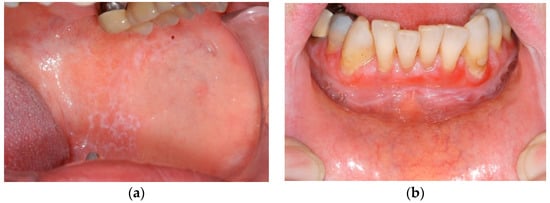

The two clinical groups in this study are based on Andreasen’s clinical classification. Group 1 represents the white variants of OLP (reticular, papular and plaque-type). They are known as the “hypokeratotic” forms (Figure 1a). The red variants of OLP are the erosive-ulcerative, the bullous and the atrophic forms. They are the so called “erosive” forms and are summarised in group 2 (Figure 1b). The most frequent clinical variant was the reticular form (group 1). Papular and plaque-type OLP did not occur in our group of patients.

Figure 1. Clinical patterns of oral lichen planus (OLP): (a) reticular and (b) erosive-ulcerative.